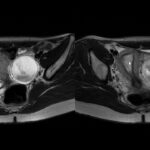

Quando descobri que estava grávida, minha médica pediu um ultrassom. Durante o exame, a pessoa que estava realizando ficou apreensiva e me perguntou se eu já sabia da existência de um cisto no ovário. Fiquei surpresa e disse que não sabia. Ela explicou que era algo bastante grande e que eu precisaria procurar um médico especialista para avaliar o que seria feito durante a gestação, pois era um pouco perigoso.

No último mês de gestação, quando completei nove meses (36 semanas), fiz outro ultrassom e descobri que o cisto tinha voltado a crescer. Estava do mesmo tamanho que antes. Nesse momento, já apresentava mais riscos e preocupações.